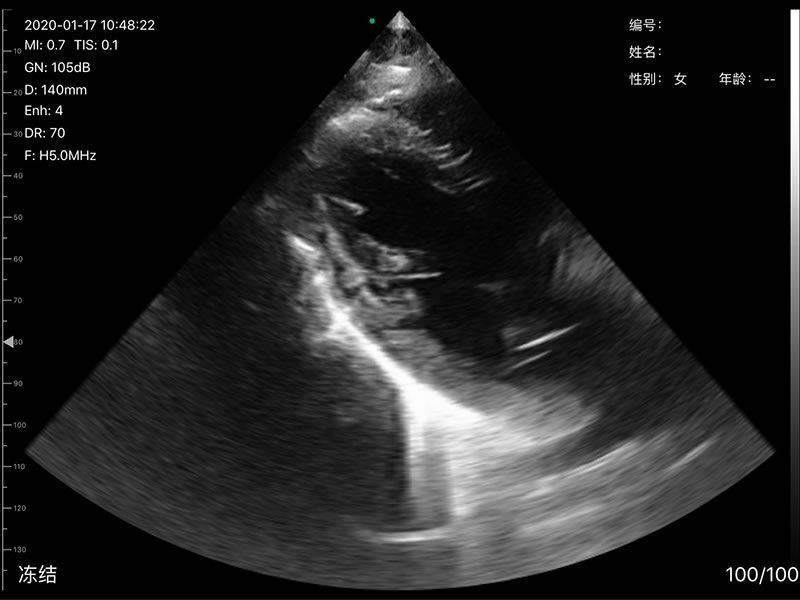

• 探头频率:凸阵/相控阵3.2/5.0MHz,线阵7.5/10MHz,心脏模式3.2-5MHZ

• 扫描深度:凸阵90/160/220/305mm,相控阵90/120/140/160,线阵20/40/60/80mm,可调

• 扫描角度和宽度:凸阵60°,相控阵80°,线阵宽度40mm